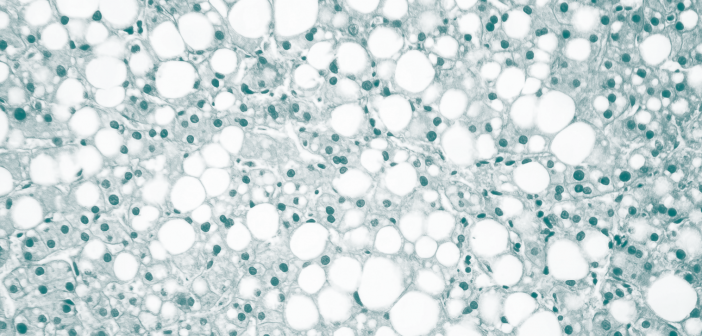

Am 12. Juni fand der globale Fettleber-Tag statt. Das Ziel seit 2018: Das öffentliche Bewusstsein für die Dringlichkeit sogenannter Steatotischer Lebererkrankungen (SLD) schärfen. Denn SLD und ihre Spätfolgen sind laut dem Global Liver Institute „eine verborgene globale Epidemie“, welche bis 2030 schätzungsweise 357 Millionen Menschen betreffen wird. Schon heute sind es laut der Deutschen Leberhilfe 20 bis 30 Prozent der Bevölkerung in den Industrienationen. Die Krux: Die Leber leidet still. „Die Symptome sind sehr unspezifisch: Müdigkeit, Abgeschlagenheit, Konzentrationsstörung“, zählt Professor Stephan Kanzler, Chefarzt der Medizinischen Klinik2 am Leopoldina-Krankenhaus in Schweinfurt, auf. Erst in fortgeschrittenen Stadien würden dem Internisten zufolge Bauchschmerzen oder Komplikationen wie Bauchwasser oder Blutungen auftreten. Doch was ist eine Fettleber? „Sie entsteht, wenn sich überflüssige Kalorien – vor allem aus Zucker und Fett – in der Leber ablagern.“ Der „harmlose“ Beginn: Die Leberzellen (Hepatozyten) nehmen Fetttröpfchen auf, die der Körper nicht mehr verarbeiten kann. Die Leber, durch die jede Minute rund eineinhalb Liter Blut fließen, wird zum Speicherort. In Industrieländern ist der häufigste Auslöser ein ungesunder Lebensstil. Professor Kanzler fasst zusammen: „Die üblichen Verdächtigen sind Bewegungsarmut, Übergewicht und Diabetes Mellitus Typ 2.“ Denkbar seien auch Begleiterscheinungen anderer Erkrankungen wie Zöliakie oder Medikamente wie unter anderem Tetrazykline. Darüber hinaus könnten genetische und hormonelle Einflüsse eine Rolle spielen. Auch Alkohol sei ein Risikofaktor – schon geringe Mengen könnten langfristig die Leber schädigen. Die Erkrankung entwickelt sich schleichend und in mehreren Stadien. Der Arzt beschreibt die Bandbreite: „Von der einfachen Fettleber (Steatose) über die Fettleberentzündung (Steatohepatitis) bis hin zum Endorganschaden – sprich Leberfibrose und -zirrhose.“ Während die einfache Fettleber häufig reversibel sei, könne eine entzündete und vernarbte Leber lebensbedrohlich werden, warnt der Gastroenterologe. Mit bildgebenden Verfahren in der Diagnostik lasse sich nicht nur der Fettgehalt, sondern auch die Gewebeelastizität gut bestimmen – beides seien wichtige Hinweise auf den Krankheitsverlauf. Biopsien seien kaum mehr nötig. Aber wie das Ruder herumreißen? „Am Anfang steht die Information über die Zusammenhänge und eine vernünftige Ernährungsberatung“, so Professor Kanzler. Wer konsequent Gewicht reduziere – etwa durch mediterrane Ernährung oder Intervallfasten – könne die Leberverfettung deutlich zurückdrängen. Auch Kaffee zeige laut Studien positive Effekte. Daneben kämen auch Medikamente zum Einsatz. Präparate wie Semaglutid oder neu entwickelte Wirkstoffe wie Resmetirom zielten auf die Reduktion der Leberfettmenge ab und würden auch bei entzündlichen Verläufen helfen. Dennoch bliebe die nachhaltigste Methode die eigene Verhaltensänderung. „Die Heilungschance ist gegen 100 Prozent“, betont Professor Kanzler mit Blick auf frühe Stadien der Erkrankung. Sei die Leber bereits vernarbt, könnten Schäden dauerhaft bleiben und im schlimmsten Fall eine Transplantation notwendig machen. Der Arzt stellt daher abschließend klar: „Die Fettleber ist keine Bagatelle, sondern eine still wachsende Gefahr – oft über Jahre unbemerkt. Mittlerweile hat sie sich zur häufigsten Ursache für Lebertransplantationen in westlichen Ländern entwickelt.“ Umso wichtiger sei es, rechtzeitig gegenzusteuern. Denn: „Kaum eine andere chronische Erkrankung ist so gut beeinflussbar.“